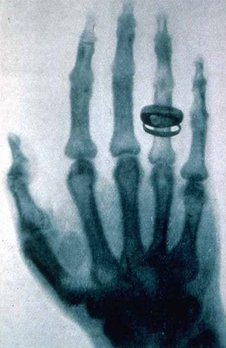

Figure g: X-rays are light waves with a very high frequency. They are absorbed strongly by bones, but weakly by flesh.